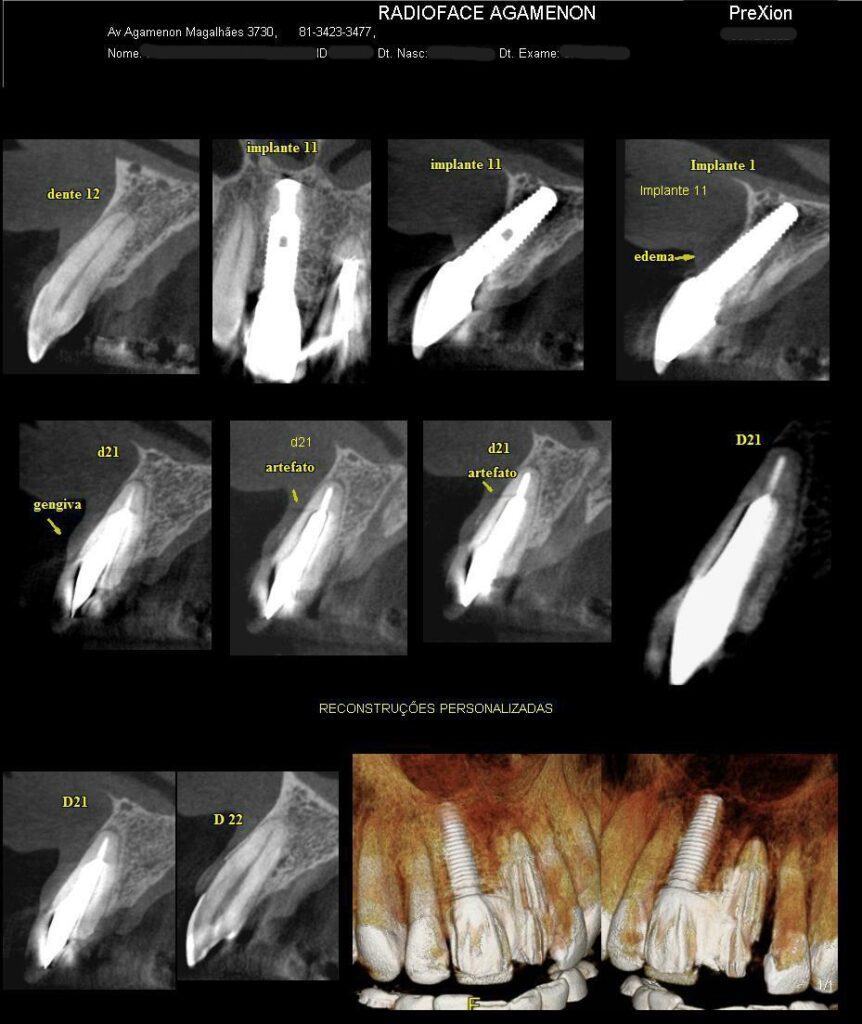

Tomografia Computadorizada

Exame Tridimensional dos Maxilares

Tomógrafo de Altíssima Resolução